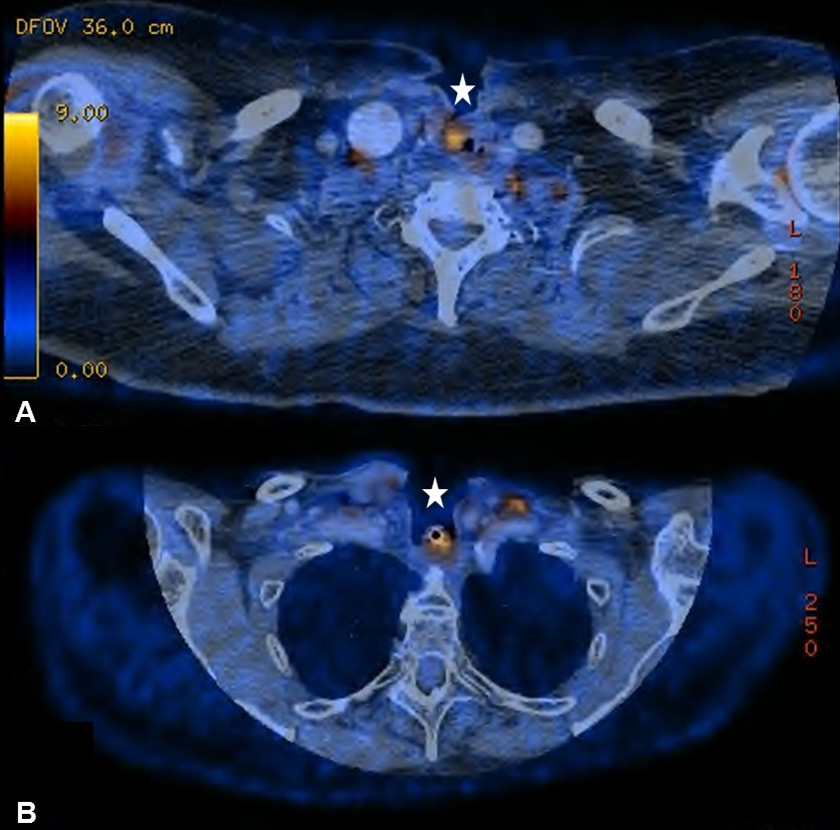

Figure 2

(A) Increased uptake in the right parotid gland in a 56-year old patient with a past medical history of radical parotidectomy and adjuvant radiation therapy (RT) on the left side due to a parotid gland carcinoma. Physiological uptake in the cervical brown fat tissue and the floor of mouth (FOM) muscles. (B) Increased uptake in the left paramedian FOM muscles due to muscular dysbalance in a 69-year old patient with a past medical history of surgical resection and RT of a right-sided base of the tongue carcinoma

It is known that PET-CT is more accurate in detecting HNC recurrence than conventional physical examinations alone and that therefore negative periodic clinical examinations may be complemented by FDG PET-CT [8, 15]. As expected, we observed PET-CT to be a well-established ruling-out test at the expense of a decreased positive predictive value and specificity [7–9]. However, interpretation of indistinct FDG-positive findings remains challenging because of a high number of false-positive lesions and the necessity for potentially unnecessary and invasive diagnostic investigations. As in previous studies, we found typical foci of increased FDG uptake [16, 17]. The pharyngeal mucosa frequently causes physiological FDG uptake, hence the interpretation is usually unproblematic as long as the uptake is located superficially along the mucosal plane in linear configuration [18]. The palatine tonsils and other lymphatic structures of the Waldeyer’s ring typically exhibit FDG uptake, which most likely reflects a so-called “physiological inflammation” of the lymphatic tissue due to confrontation with antigens [18, 19] (fig. 1A). Furthermore, muscles of mastication and intrinsic tongue muscles were shown to be highly sensitive to exogenous confounders such as chewing gum during examination and therefore a good quality of PET-CT/MRI clearly depends on the compliance of the patient [20, 21] (fig. 1B). With regard to the floor of mouth (FOM) muscles, a recent study investigating the effect of a supine versus a sitting position on physiological FDG accumulation, did not find any alterations and concluded that there is no trick to avoid or reduce this kind of disturbing FDG uptake [22]. The correlation between muscular activity and increased FDG uptake was also shown for the larynx, since talking can cause FDG uptake in the muscles of phonation as well as in the vocal cords [18, 23]. In terms of FDG uptake in the salivary glands, the parotid, submandibular and sublingual glands may all reveal mild to moderate symmetric or asymmetric uptake, although these findings underlie a marked inter-individual variability [16, 17]. As there is a close relationship between reduction in FDG uptake into the salivary glands and increasing doses of RT, we found five patients with asymmetric salivary gland FDG uptake due to surgical treatment and RT to the contralateral side [24] (fig. 2A). Similarly, we observed four patients with asymmetric FDG uptake in the tongue and FOM as a consequence of muscular imbalance due to contralateral surgical treatment (fig. 2B). Another well-known phenomenon is the increased FDG uptake in the contralateral vocal cord if a recurrent laryngeal nerve palsy is present (fig. 3AB).